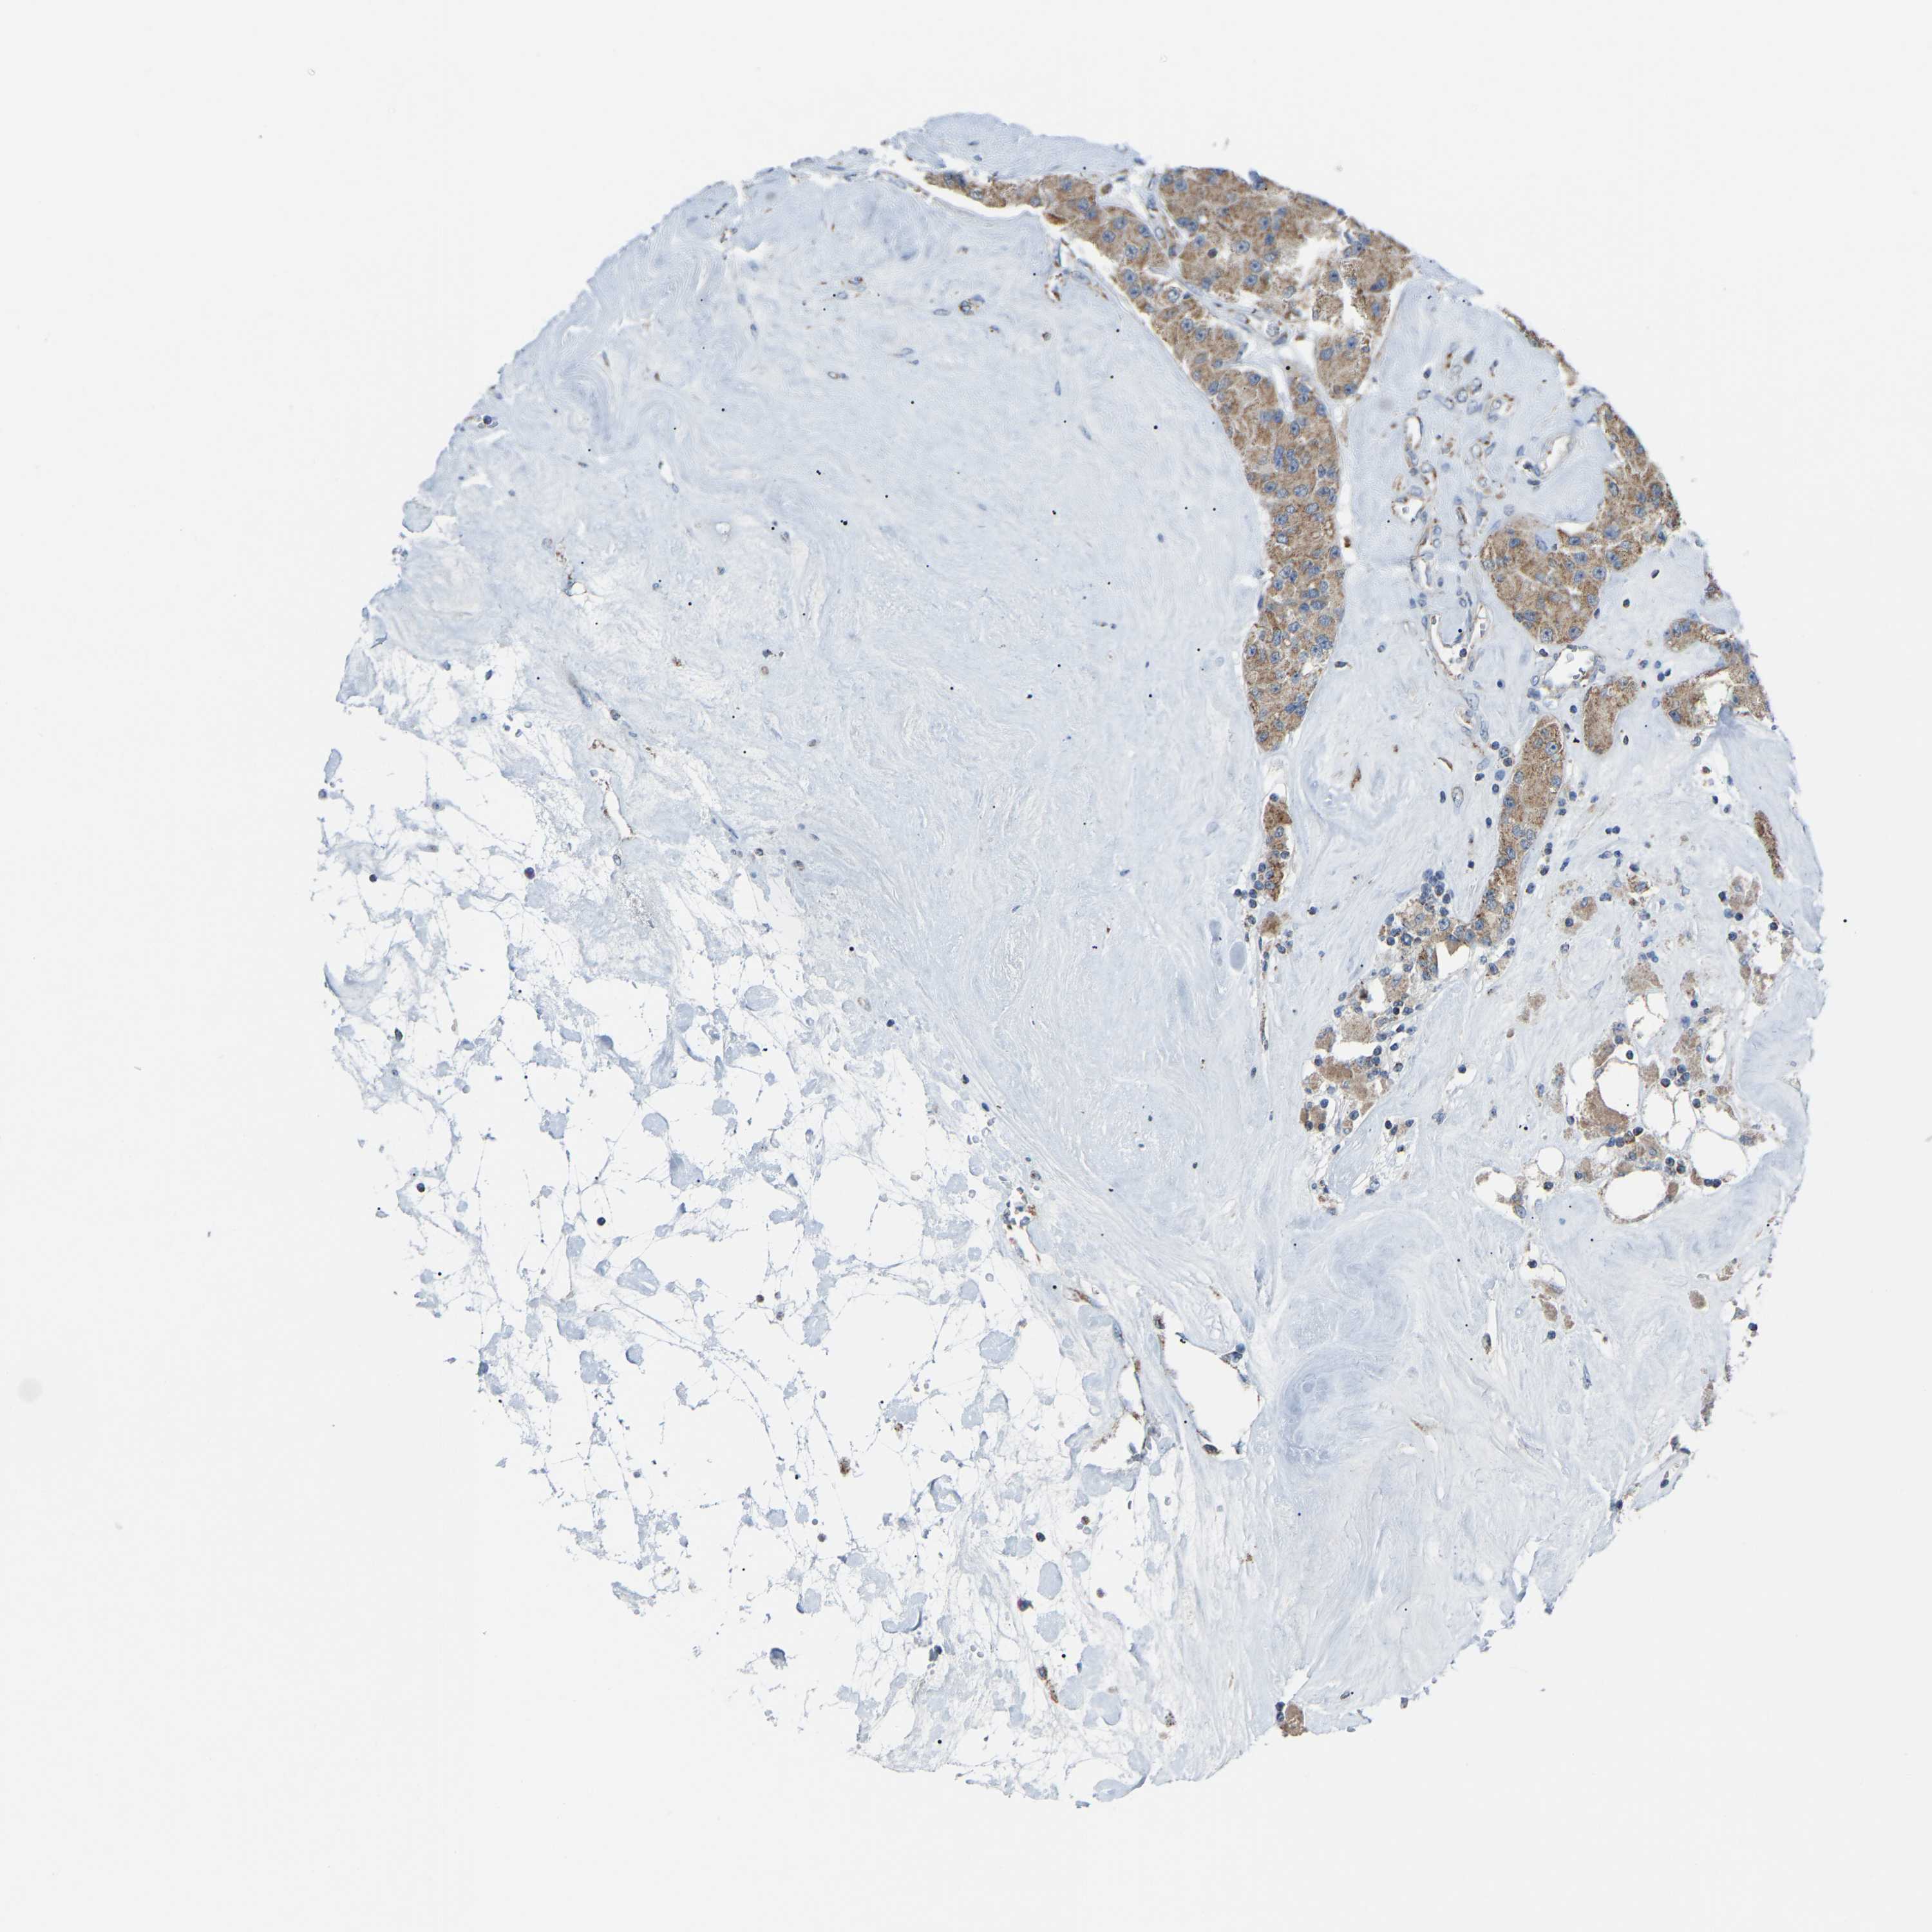

CANT1